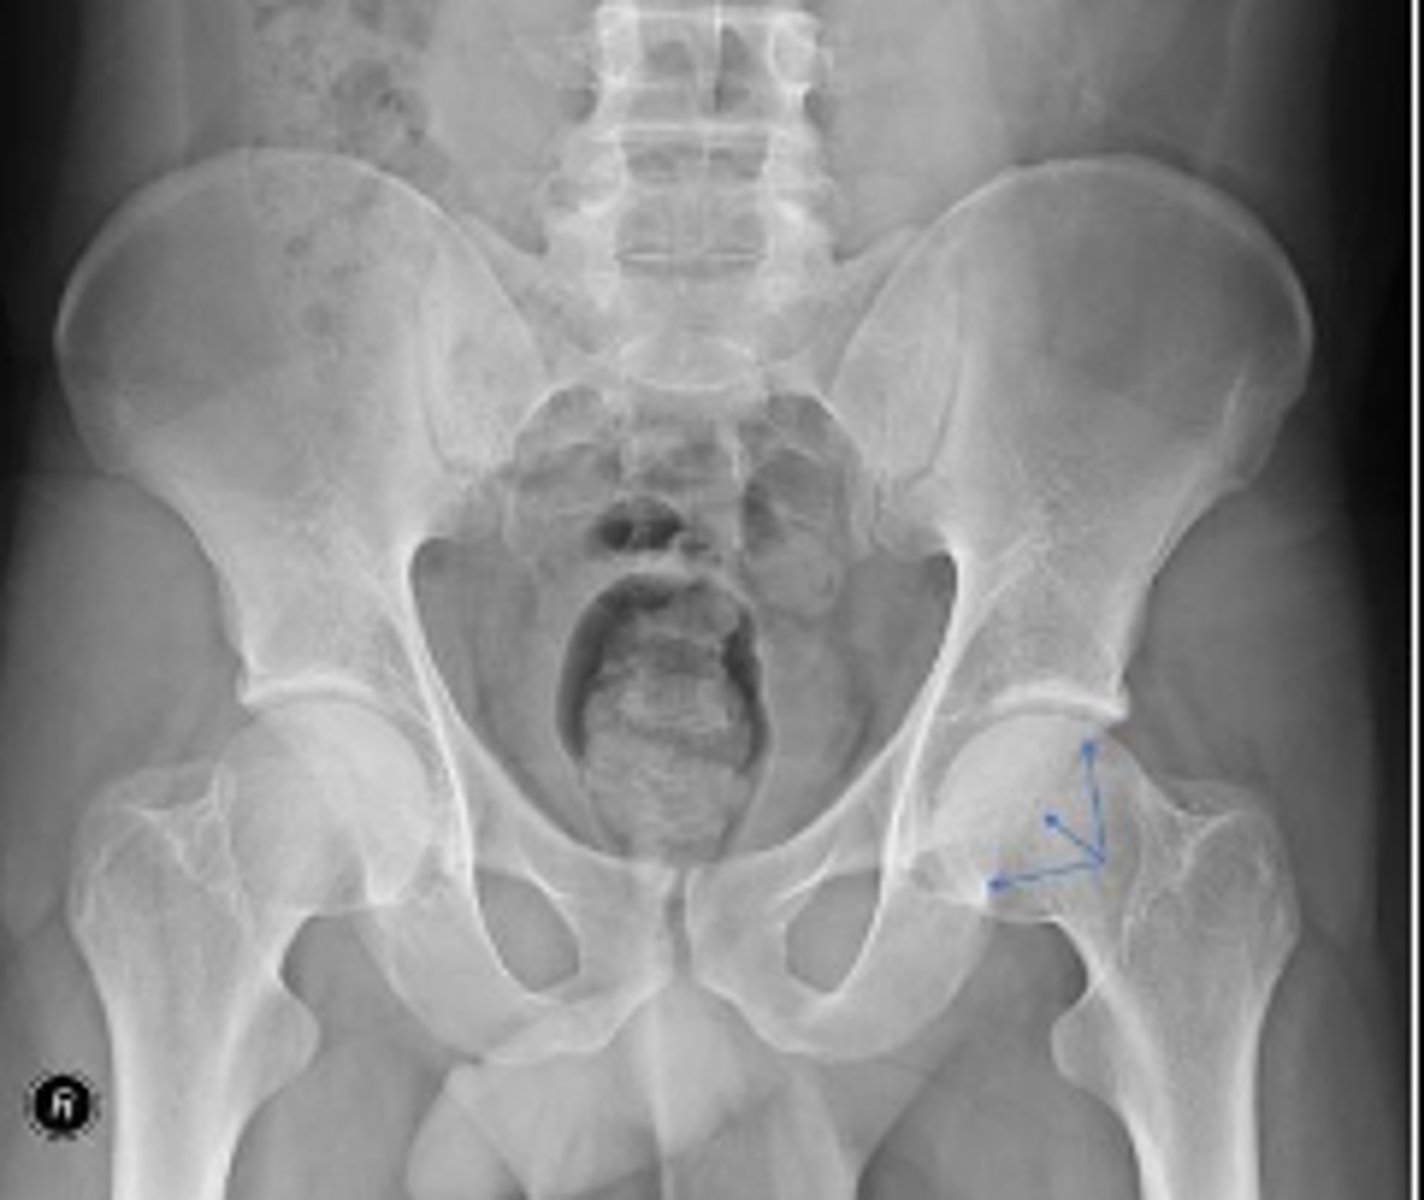

Right AP hip

What is the name of the radiographic view?

Right frog-leg hip

Left and right posterior inferior iliac spine

What are the arrows pointing to?

Posterior rim of the left acetabulum

Right ischial spine

Posterior rim of the right acetabulum

Anterior rim of the right acetabulum

Right sacroiliac joint space

What joint space is the arrow pointing to?

Lesser trochanter of the right femur

Greater trochanter of the right femur

Right posterior inferior iliac spine

Intertrochanteric line of the right femur

Right ischial tuberosity